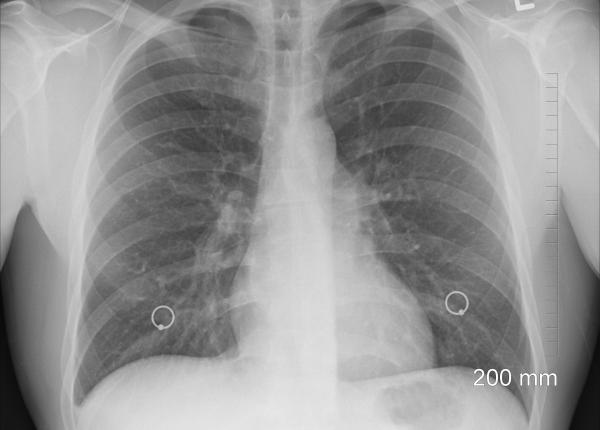

În perioada 15–17 februarie, se va desfășura cea de-a doua ediție a târgului Zilele Baby Sanador, destinat viitoarelor mămici. Evenimentul va fi găzduit de Centrul de Conferinț...